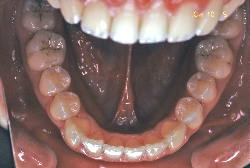

叢生(そうせい)

凸凹な歯並びのことを叢生といいます。矯正歯科に来院する患者様の主訴の中で、最も多いのが「配列の凸凹を真っ直ぐにしたい」というものです。歯の大きさと顎の大きさの調和がとれていないことが原因です。

凸凹を主体としたケースの場合、当院の平均治療期間は18ヶ月ですので、このケースは少し長めに経過しました。理由の一つは凸凹の程度がかなり重症だったと言うことですが、もう一つは、右下第2大臼歯が45度くらい前傾していたため、それを整直化させるために時間を要したと考えています。いずれにしても最終結果は大変よい状態と思います。

治療前は並びが乱れて見た目が悪いというのはもちろん問題ですが、歯科医学的に一番困るのは噛み合わせが悪いという点です。上下の犬歯(3番目の歯)は、上下的に離れた位置にあるため接触することができません。つまり歯としては存在していても、歯としては機能していないということです。